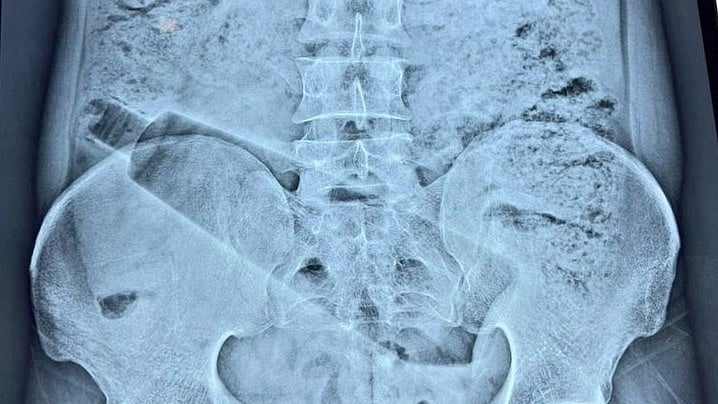

Người đàn ông 38 tuổi, cư dân của khu Saket Colony, được cho là đã bị đau bụng dữ dội trong gần 36 giờ trước khi được đưa đến một bệnh viện tư nhân. Thăm khám ban đầu và chụp X-quang cho thấy một chai nhựa dung tích một lít bị mắc kẹt bên trong cơ thể ông.

Chiếc chai nhựa mắc kẹt trong cơ thể của người đàn ông.